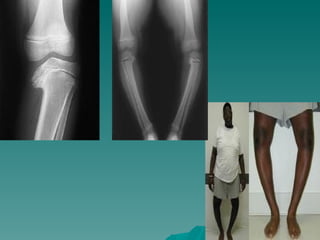

Blount hastalığı

   Blount tibia vara’yı tibia proksimal medial

    metafizin enkondral ossifikasyonunda

Neden?: kalıtımsal + gelişimsel

Enfeksiyon,Travma,AVN,Riketsin latent

formu

 Erken yürüme + obesite ile ilişkisi var

   Tibiada varus + internal torsiyon + genu

Blount hastalığı  Blount tibia vara’yı tibia proksimal medial epifizinin osteokondrozu olarak tarif etmiş  metafizin enkondral ossifikasyonunda bozukluk Neden?: kalıtımsal + gelişimsel Enfeksiyon,Travma,AVN,Riketsin latent formu  Erken yürüme + obesite ile ilişkisi var  Tibiada varus + internal torsiyon + genu rekuvatum